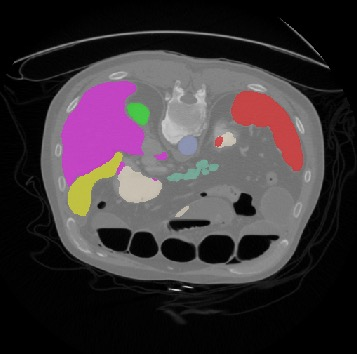

Transformers, the default model of choices in natural language processing, have drawn scant attention from the medical imaging community. Given the ability to exploit long-term dependencies, transformers are promising to help atypical convolutional neural networks (convnets) to overcome its inherent shortcomings of spatial inductive bias. However, most of recently proposed transformer-based segmentation approaches simply treated transformers as assisted modules to help encode global context into convolutional representations without investigating how to optimally combine self-attention (i.e., the core of transformers) with convolution. To address this issue, in this paper, we introduce nnFormer (i.e., Not-aNother transFormer), a powerful segmentation model with an interleaved architecture based on empirical combination of self-attention and convolution. In practice, nnFormer learns volumetric representations from 3D local volumes. Compared to the naive voxel-level self-attention implementation, such volume-based operations help to reduce the computational complexity by approximate 98% and 99.5% on Synapse and ACDC datasets, respectively. In comparison to prior-art network configurations, nnFormer achieves tremendous improvements over previous transformer-based methods on two commonly used datasets Synapse and ACDC. For instance, nnFormer outperforms Swin-UNet by over 7 percents on Synapse. Even when compared to nnUNet, currently the best performing fully-convolutional medical segmentation network, nnFormer still provides slightly better performance on Synapse and ACDC.